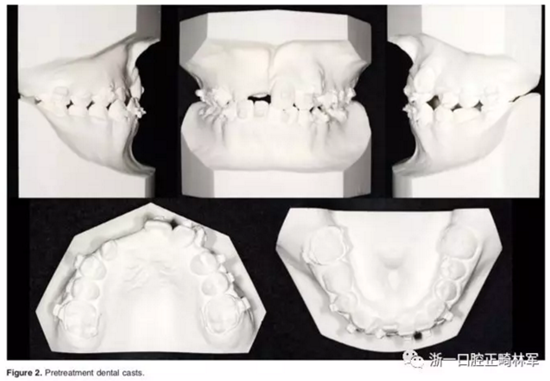

口內(nèi)相示:替牙晚期,11-13未萌,磨牙端端關(guān)系,前牙擁擠嚴(yán)重,23高位,53、75滯留;患者正采用固定矯治,部分托槽有脫落。

全景X片及CBCT示:11-13復(fù)雜阻生,上頜前牙區(qū)牙槽骨水平不足;11阻生,遠(yuǎn)中旋轉(zhuǎn)90°,牙冠朝向腭側(cè),根尖位于鼻底、前鼻棘皮質(zhì)骨內(nèi),牙根形態(tài)彎曲;12、13不完全易位,12位置偏腭側(cè),13位置偏舌側(cè),12的牙根形態(tài)也較彎曲。